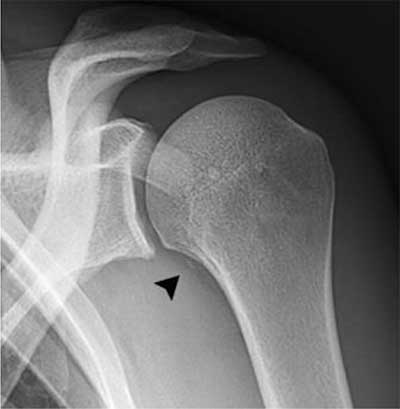

Figure 1

A 29-year-old rugby player presenting after shoulder trauma. Standard radiography of the left shoulder. A small fleck of bone (black arrowhead) is seen medial to the proximal humerus.

Standard radiography in the acute phase may reveal a small subtle fleck of bone at the periosteal insertion of the teres major. This should not be misinterpreted as a bony Bankart lesion, as the lesion is located slightly more inferiorly. CT may be useful to diagnose a subtle avulsion and for follow-up showing progressive peripheral calcification and ossification and ultimately fusion with the underlying cortex [4]. Although MR (arthrography) is currently a routine imaging tool for evaluation of shoulder trauma in sports trauma, it is important to analyze the images beyond the margin of the joint and scrutinize for extra-articular lesions [8]. Therefore, at least one imaging sequence with a large field of view should be used.